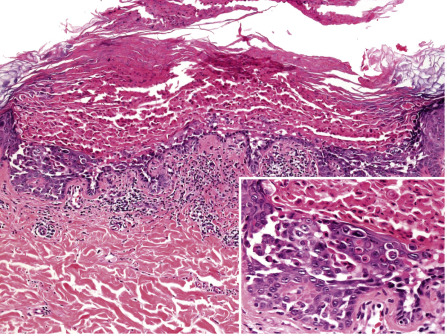

There are two prominent histologic features in Darier disease, acantholysis and dyskeratosis ( Fig. 59.13 ). Acantholysis is due to a disturbance in cell adhesion that leads to suprabasilar cleft formation. At the ultrastructural level, this corresponds to a loss of desmosomes and detachment of keratin filaments from the desmosomes . Dyskeratosis is due to apoptosis of keratinocytes and is characterized by nuclear condensation and perinuclear keratin clumping. Two types of dyskeratotic cells are observed in Darier disease :

“Corps ronds” – acantholytic enlarged keratinocytes in the malpighian layer with darkly staining and partially fragmented nuclei surrounded by a clear cytoplasm and encircled by a bright ring of collapsed keratin bundles.

“Grains” – small, oval cells in the stratum corneum characterized by an intensely eosinophilic cytoplasm composed of collapsed keratin bundles containing shrunken parakeratotic nuclear remnants. “Grains” are likely derived from “corps ronds”, but formal proof that they indeed represent different stages of the same pathologic process has not been provided.

The epidermis overlying acantholytic and dyskeratotic foci is thickened and shows papillomatosis and hyperkeratosis. In the superficial dermis, there is a mild to moderate perivascular inflammatory infiltrate. Diagnostic histologic changes are often focal, necessitating a careful search. Similar histologic features may be observed in Grover disease, but in the latter there tends to be more acantholysis, less dyskeratosis, and fewer “corps ronds” or “grains”. The two conditions can be histologically indistinguishable, but the findings are typically more pronounced, widespread, and follicle-based in Darier disease.